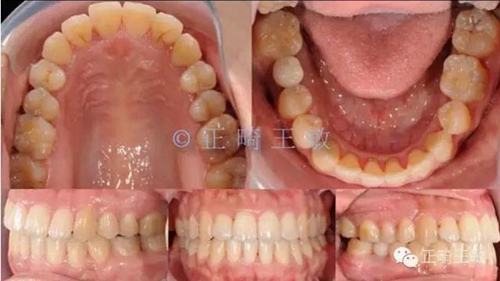

有了一個(gè)目標(biāo)后,矯正就很簡(jiǎn)單了,拔掉一顆牙,7個(gè)月順利讓牙齒移動(dòng)到我們想要的位置:

9.jpg

雖然這個(gè)時(shí)候正畸并沒(méi)有結(jié)束,但對(duì)于種植來(lái)說(shuō),間隙和排列,已經(jīng)足夠了,畢竟種植周期也要4個(gè)月,后面的治療就是繼續(xù)關(guān)閉間隙,調(diào)整咬合,同時(shí)等著那顆種植牙生根發(fā)芽。來(lái)看看最終的樣子: